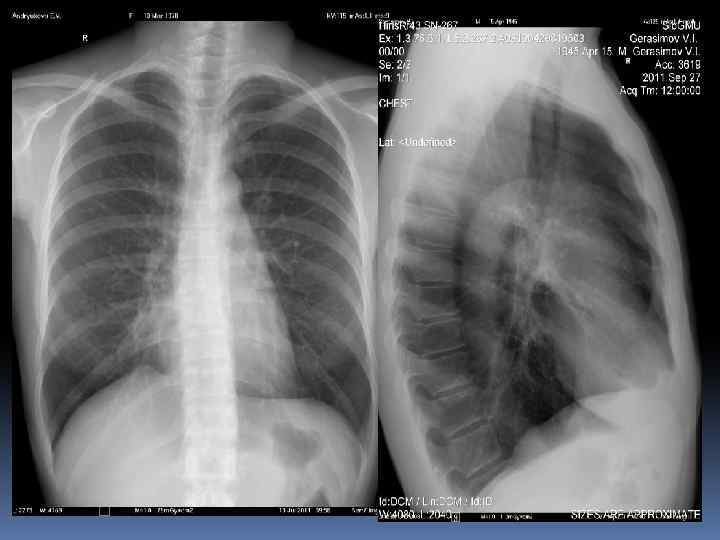

Легочной рисунок Легочные поля имеют определенную структуру – легочной рисунок. Главной основой этих теней легочного рисунка являются кровеносные сосуды в различных проекциях; к последним относятся не только тени артериальной, но и венозной системы. Ø Легочной рисунок – понятие чисто рентгенологическое. Ø Легочные поля имеют хорошо выраженный, богатый и сложный легочный рисунок. В основном он представлен тяжеобразными переплетающимися тенями, более интенсивными и крупными в медиальных отделах. Ø К периферическим участкам легочных полей количество ветвящихся теней убывает из-за уменьшения их диаметра, в плащевой зоне лёгкого в норме легочного рисунка нет. Ø Кроме того, легочной рисунок лучше всего выражен в нижних полях, где расположена большая часть сосудов, толще легочная паренхима, где кровенаполнение больше. Ø Наряду с этими продолговатыми тенями, в легочных полях имеются округлые или овальные интенсивные тени – сосуды в поперечном сечении, которые следует отличать от очаговых патологических образований.

Легочной рисунок. Главной основой теней легочного рисунка являются кровеносные сосуды в различных проекциях:

ØНаряду с этими продолговатыми тенями, в легочных полях имеются округлые или овальные интенсивные тени – сосуды в поперечном сечении, которые следует отличать от очаговых патологических